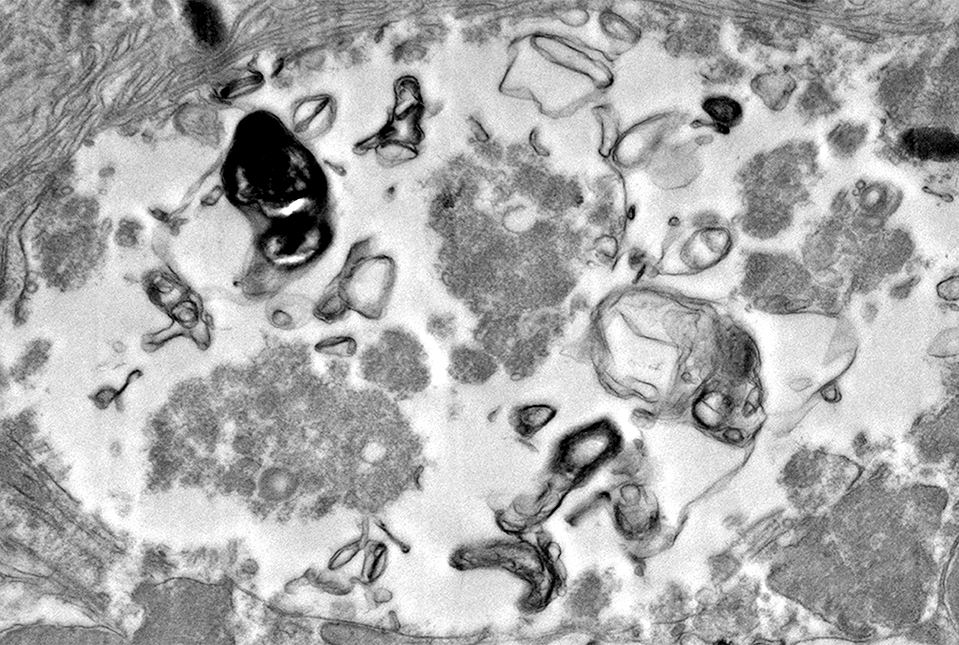

The researchers observed that even in young mice, the rods lacking VPS35 soon lost their synapses—connection points to other neurons—resulting in visual impairment similar to seen in patients with Parkinson’s. Alpha-synuclein aggregates began to form, and eventually, as the affected rods began to die, the mouse retinas showed large, insoluble inclusions that looked like Lewy bodies, which contain alpha-synuclein aggregates and are one of the classic pathological signs of Parkinson’s disease.

The findings with the new model also point to a potential new strategy for detecting Parkinson’s disease. Even in three-month old mice lacking rod-cell VPS35, the researchers could use a standard ophthalmological device called a fundoscope to observe bright spots of “autofluorescence” caused by molecules called lipofuscin, which associate with alpha-synuclein aggregates. Dr. Sung and her international physician collaborators are currently planning a clinical trial of this approach.